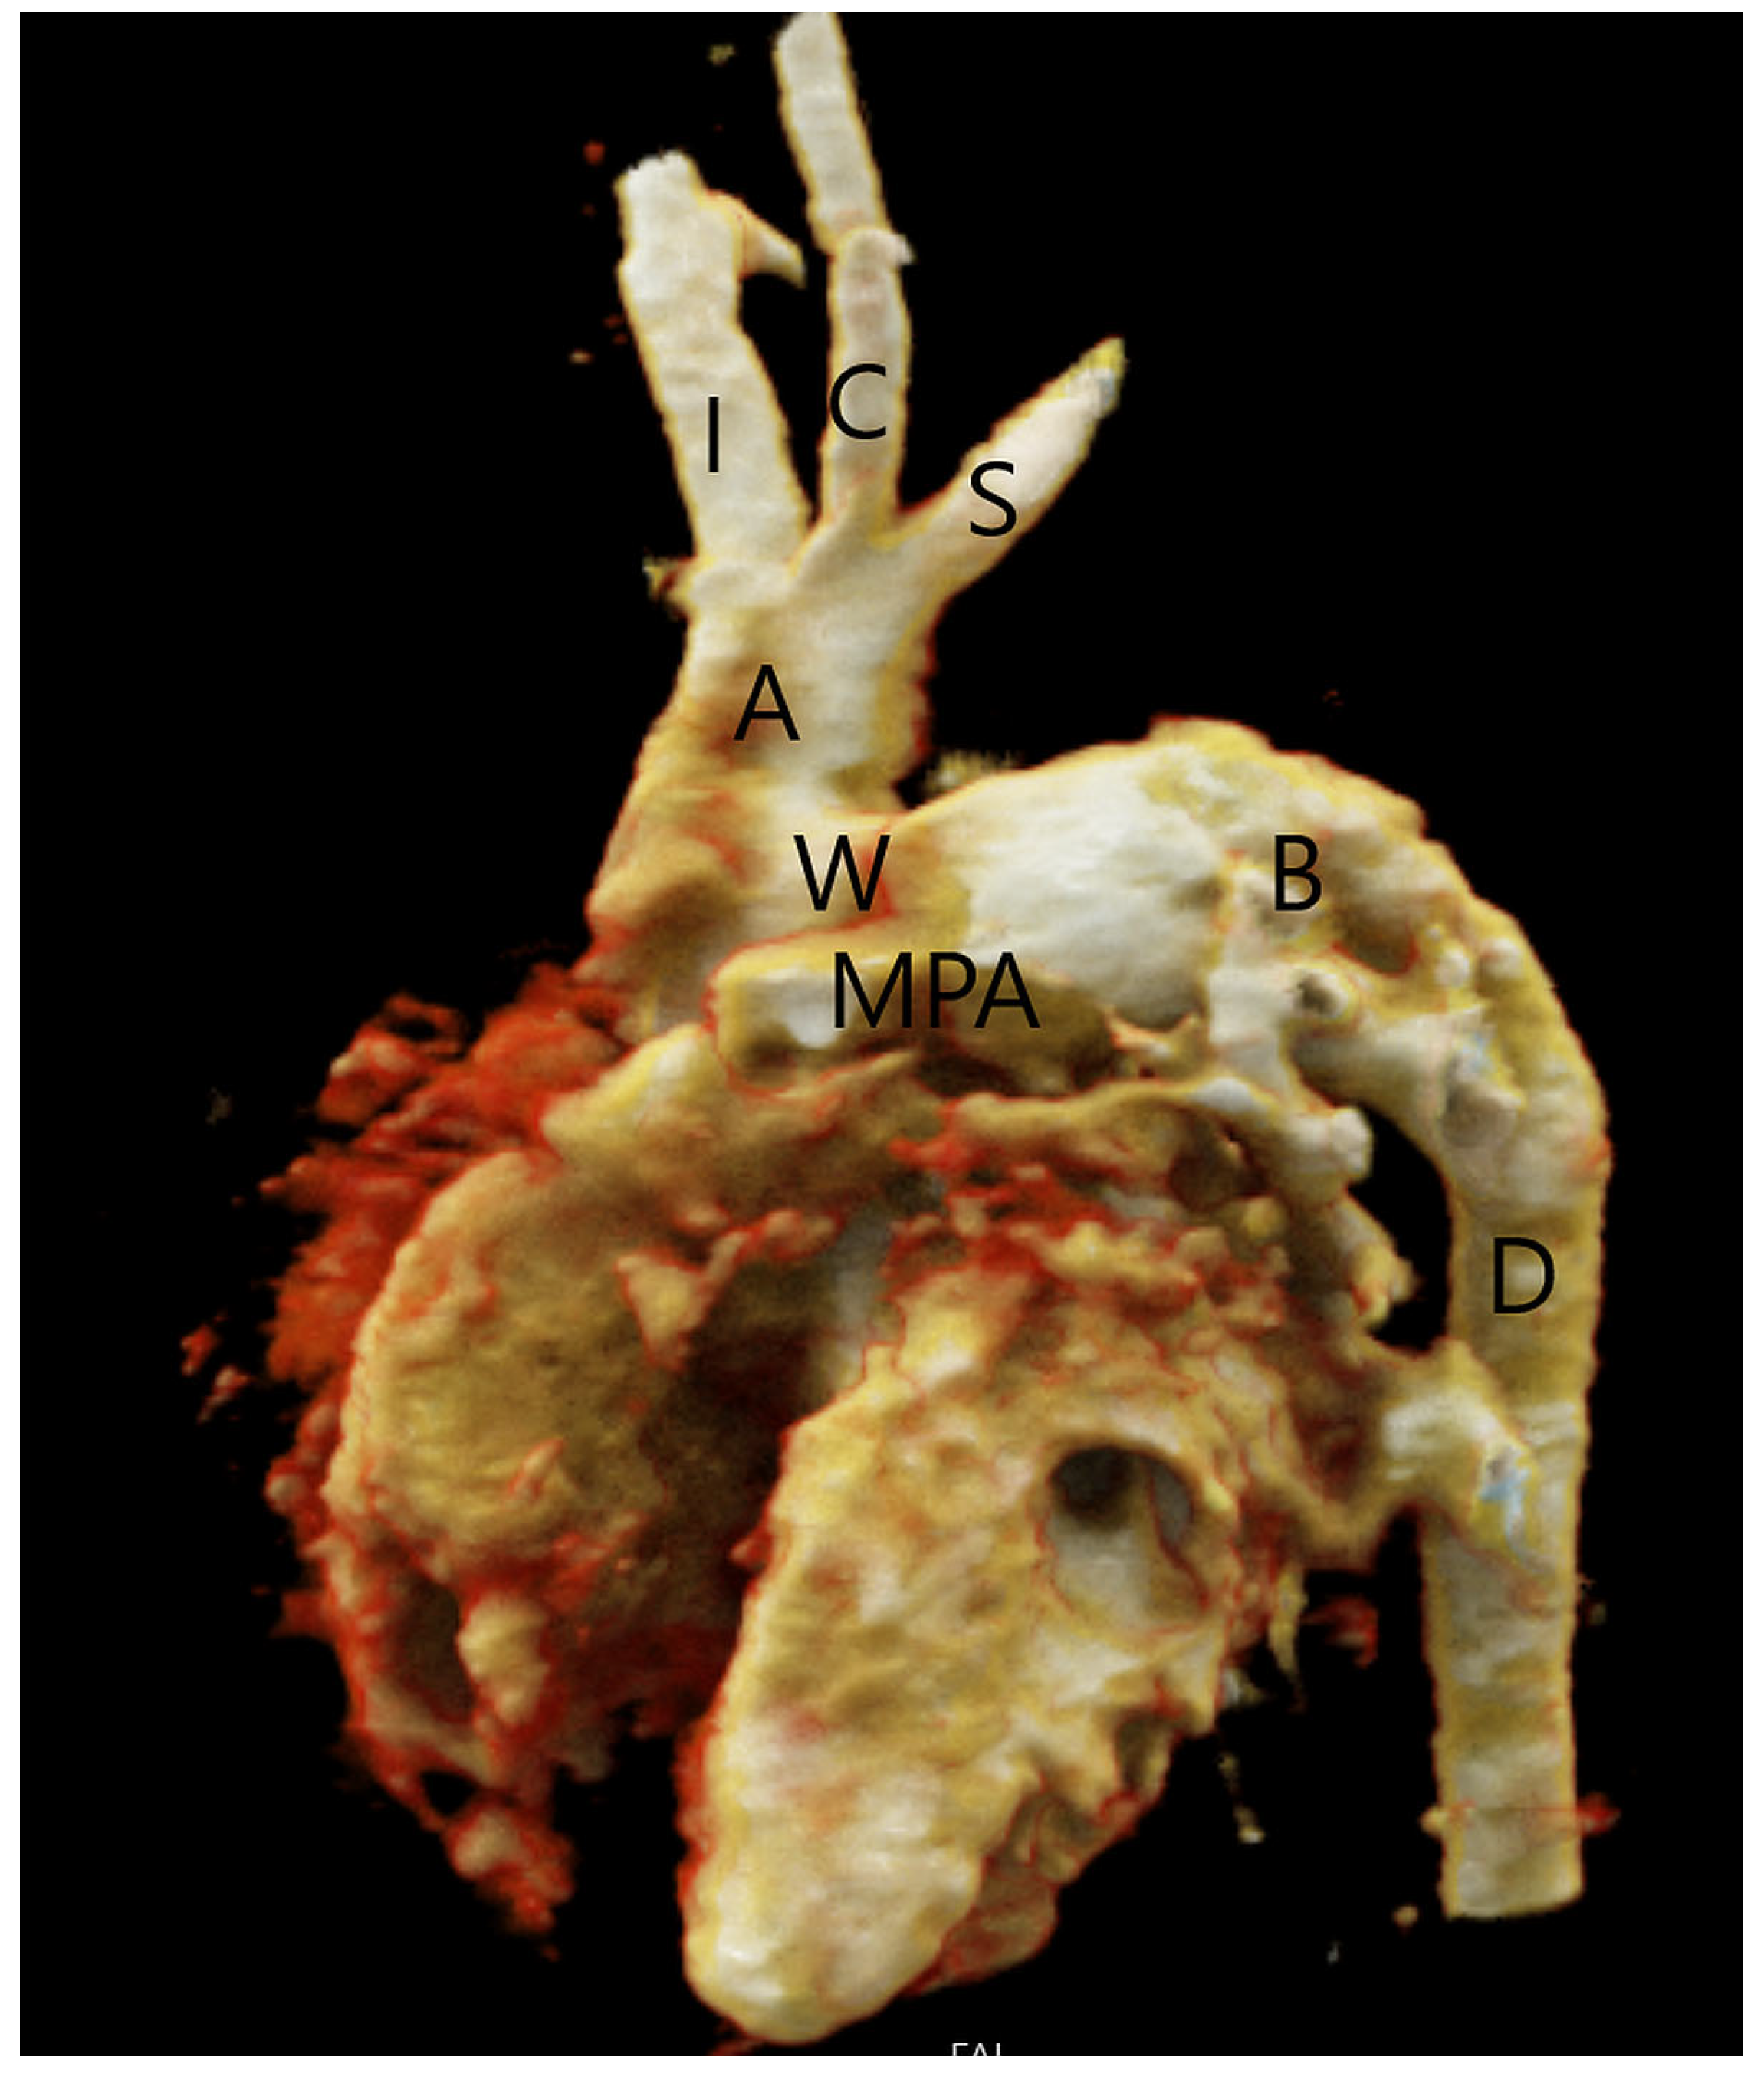

The aortopulmonary window presents as either an isolated anomaly or in association with other anomalies. Around 50% of the patients have associated cardiovascular anomalies requiring surgical repair, of which the most common are type A interrupted aortic arch distal to the left subclavian artery (Figure 4) and aortic coarctation that are present in 10–15% of patients with aortopulmonary septal defect [5]. In these patients, flow to the caudal part of the body is preserved through the aortopulmonary window and then via the patent ductus arteriosus to the descending aorta. Therefore, these patients require prostaglandin therapy to maintain ductal patency and blood supply of the caudal part of the body. In patients with associated aortic arch abnormalities, a cardiogenic shock may occur if the ductus arteriosus closes. Other associated anomalies described in the literature include tetralogy of Fallot, the right aortic arch, transposition of the great arteries, ASD, VSD, and an abnormal origin of the coronary arteries that may arise from the edge of the defect on the aortic or pulmonary artery side of the defect [5,34]. For that reason, the imperative is to correctly assess the anatomical relationship between the aorta and pulmonary artery, as well as those of the heart, great vessels, and aortic arch.

Figure 4.

Type A interrupted aortic arch in a patient with aortopulmonary septal defect type 2 (W), volume rendering reconstruction of CT angiography. The aorta (A) ends distally to the origin of the left subclavian artery (S). The descending aorta (D) is supplied by the patent ductus arteriosus (B). Main pulmonary artery (MPA), innominate artery (I), and left common carotid artery (C).